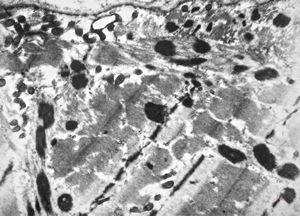

F,32y. | transversally sectioned skeletal muscle cell

mouse skeletal muscle cell - transversal section